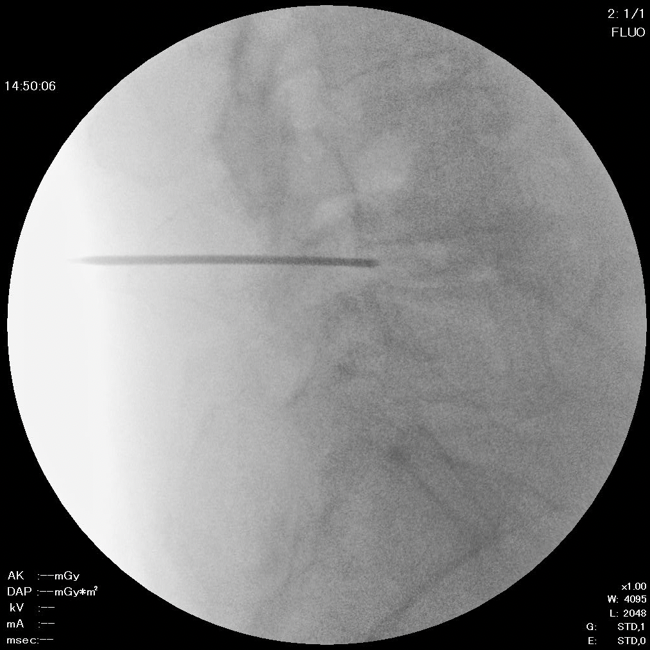

2. ニードル留置

直径約2mmのニードルを椎間板に留置します。

治療時間は約20〜30分です。

局所麻酔で行うため痛みは最小限に抑えられます。

神経に近い部位では、その部位に広がるような痛みを感じることがあります。その際は必ずお知らせください。